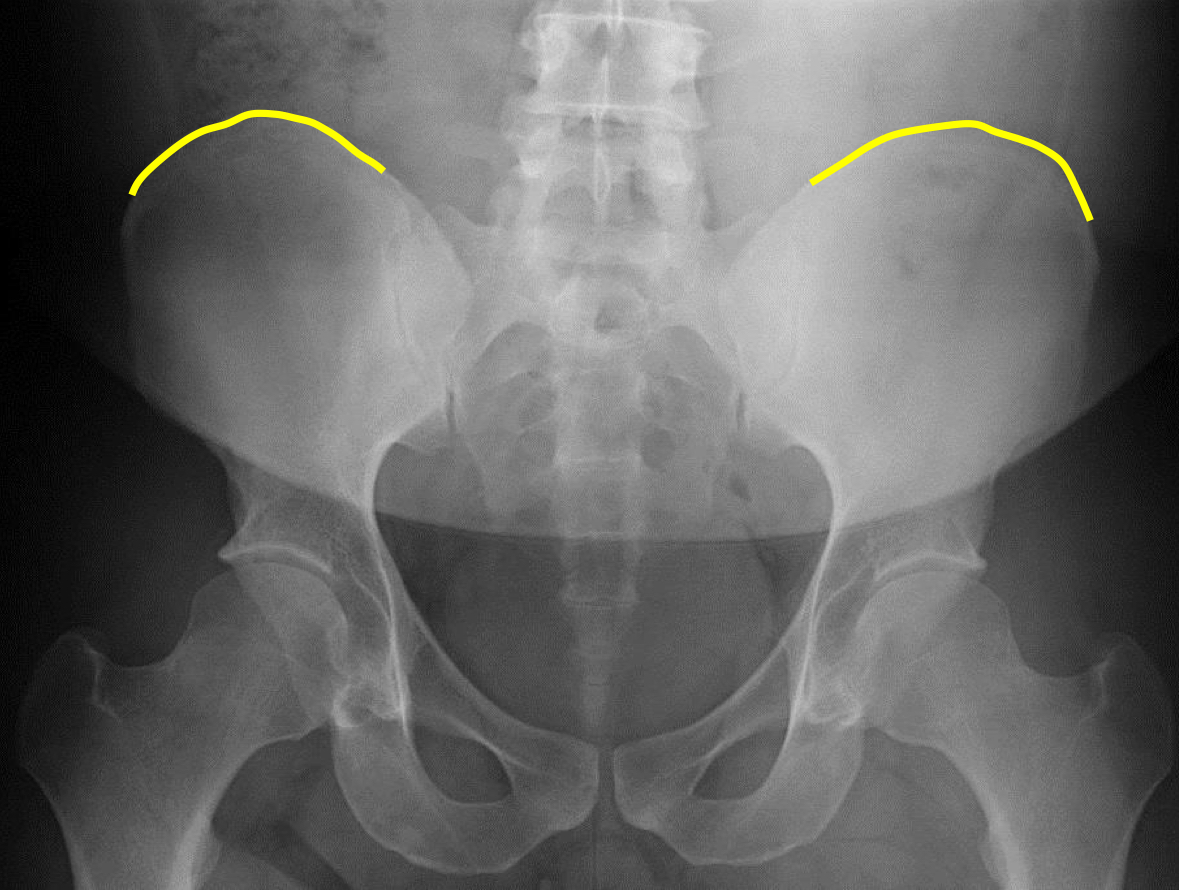

What view is this?

AP (Anterior to Posterior) LumboPelvic

What is this?

Superior Iliac Crests

What is this?

Lateral Iliac Crests

What is this?

Ischial Tuberosites

What is this?

Obturator Foramen

What is this?

S2 Tubercle

What is this?

Pubic Symphysis

What is this?

Sacral Groove

What is this?

Lateral aspect of sacrum

What is this?

Medial Aspect of Ilium